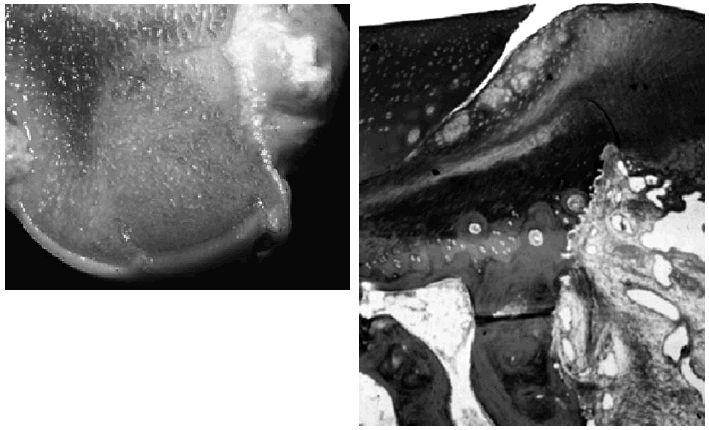

Por otro lado, a nivel histológico, el trasplante no tiene una incorporación perfecta. Existe una falta de unión entre el cartílago injertado y el que le rodea. Aunque esta falta de «cicatrización» del tejido cartilaginoso es un hecho conocido, se ha comprobado recientemente su constancia al utilizar esta técnica en animales21,22 (Fig. 5). Quizás en un futuro las técnicas de fusión tisular con láser, actualmente en vías de experimentación o a aplicación de factores de crecimiento pueda mejorar esta interfaz. También cabe señalar que con la mosaicoplastia no se reproduce un tejido uniforme sino un material «compuesto», al estar los espacios rellenos por fibrocartílago de peores cualidades para resistir cargas, y que esta extensión puede representar en ocasiones más de un tercio de la superficie trasplantada6 (Fig. 6).

Figura 5. A: Cóndilo femoral de un cordero en el que macroscópicamente se aprecia la perfecta incorporación del cilindro osteocondral. B: Microscópicamente se aprecia la falta de unión entre el cartílago hialino del injerto y la zona vecina (Cedidas por F. Forriol).